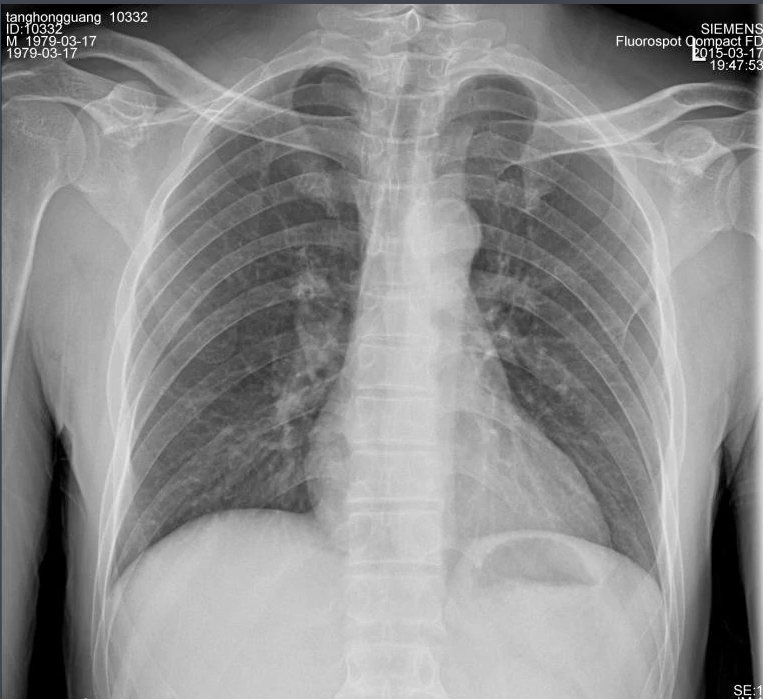

X射线因其波长短,能量大,照在物质上时,仅一部分被物质所吸收,大部分经由原子间隙而透过,表现出很强的穿透能力。X射线穿透物质的能力与X射线光子的能量有关,X射线的波长越短,光子的能量越大,穿透力越强。X射线的穿透力也与物质密度有关,利用差别吸收这种性质可以把密度不同的物质区分开来 。

X射线同可见光一样能使胶片感光。胶片感光的强弱与X射线量成正比,当X射线通过人体时,因人体各组织的密度不同,对X射线量的吸收不同,胶片上所获得的感光度不同,从而获得X射线的影像 。